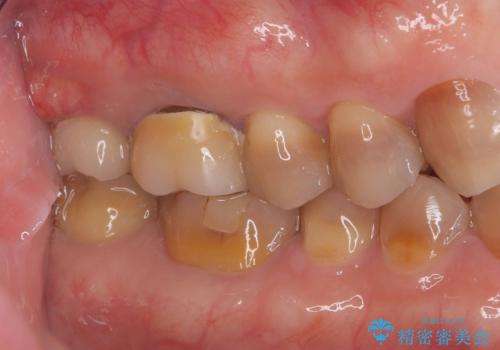

抜歯と歯根嚢胞の除去を行った後、インプラントで治療しました。治療後は「自分の歯のように咬める」と大変ご満足いただけました。